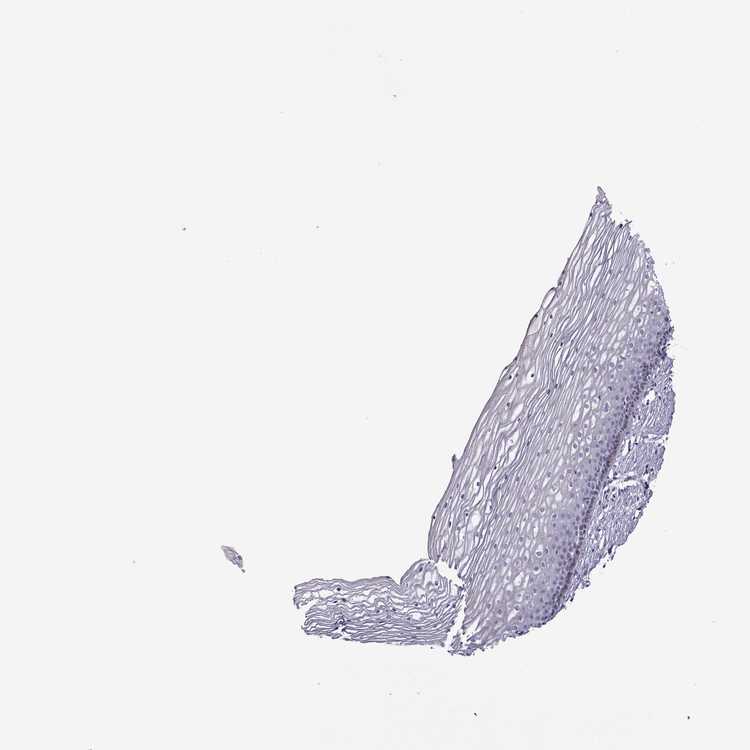

TISSUE PRIMARY DATA CERVIX Show tissue menu

Cervix

CERVIX - Expression summary

CERVIX - Antibody stainingi

Antibody staining in the annotated cell types in the current human tissue is reported as not detected, low, medium, or high, based on conventional immunohistochemistry profiling in selected tissues. This score is based on the combination of the staining intensity and fraction of stained cells.

Each image is clickable and will lead to virtual microscopy that enables deeper exploration of all samples and also displays staining intensity scores, fraction scores and subcellular localization as well as patient and tissue information for each sample.

Antibody HPA037582Antibody HPA070304

Squamous epithelial cells Not detectedNot detected